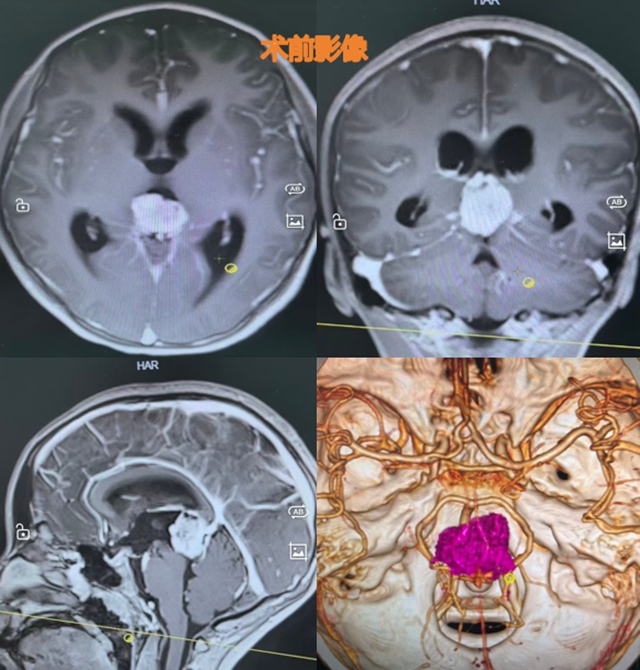

面对如此复杂棘手的病例,西南医科大学附属医院神经外科迅速组织了多学科会诊,经过神经内科郭晓燕副教授、肿瘤科郑芸主治医师、影像科赵冬梅主治医师及病理科郭庆喜副教授等一番深入研讨和“头脑风暴”,提出:小汪的疾病高度怀疑为松果体区生殖细胞恶性肿瘤同时伴有梗阻性脑积水。按照治疗指南,首先要开颅手术取得病理活检标本,明确诊断,同时要解决梗阻性脑积水问题,以缓解颅内高压,为后续治疗争取时间。

手术分为两部分进行。第一部分,龚飞龙等医生通过脑室镜在小汪的三脑室底部开放一通道,将脑积水强行改道,顺利解决脑积水问题。

由于肿瘤血供极为丰富,术中情况极不稳定,继续操作将显著增加出血、脑损伤等风险。为保障患者安全,团队及时调整手术策略,中止切除,并依据术中脑组织肿胀情况,去除部分颅骨骨瓣,以缓解颅内压力,为后续康复治疗创造条件。

肿瘤若不及时治疗,发展速度极快。结合术中所见及影像、病理等多学科综合判断,病灶性质复杂。鉴于患者术后状态尚不稳定,常规放化疗实施条件暂不成熟。经过评估,最终决定采用伽玛刀放射治疗。

据龚飞龙介绍,伽马刀放射治疗具有单次剂量高、治疗周期短的优势,对于术后情况不稳定、无法承受普通放疗多次治疗的小汪来说,无疑是最可行的方案。为缩短单次治疗时间,保证小汪安全,医生决定分两次进行伽马刀放射治疗,中间仅间隔5天。